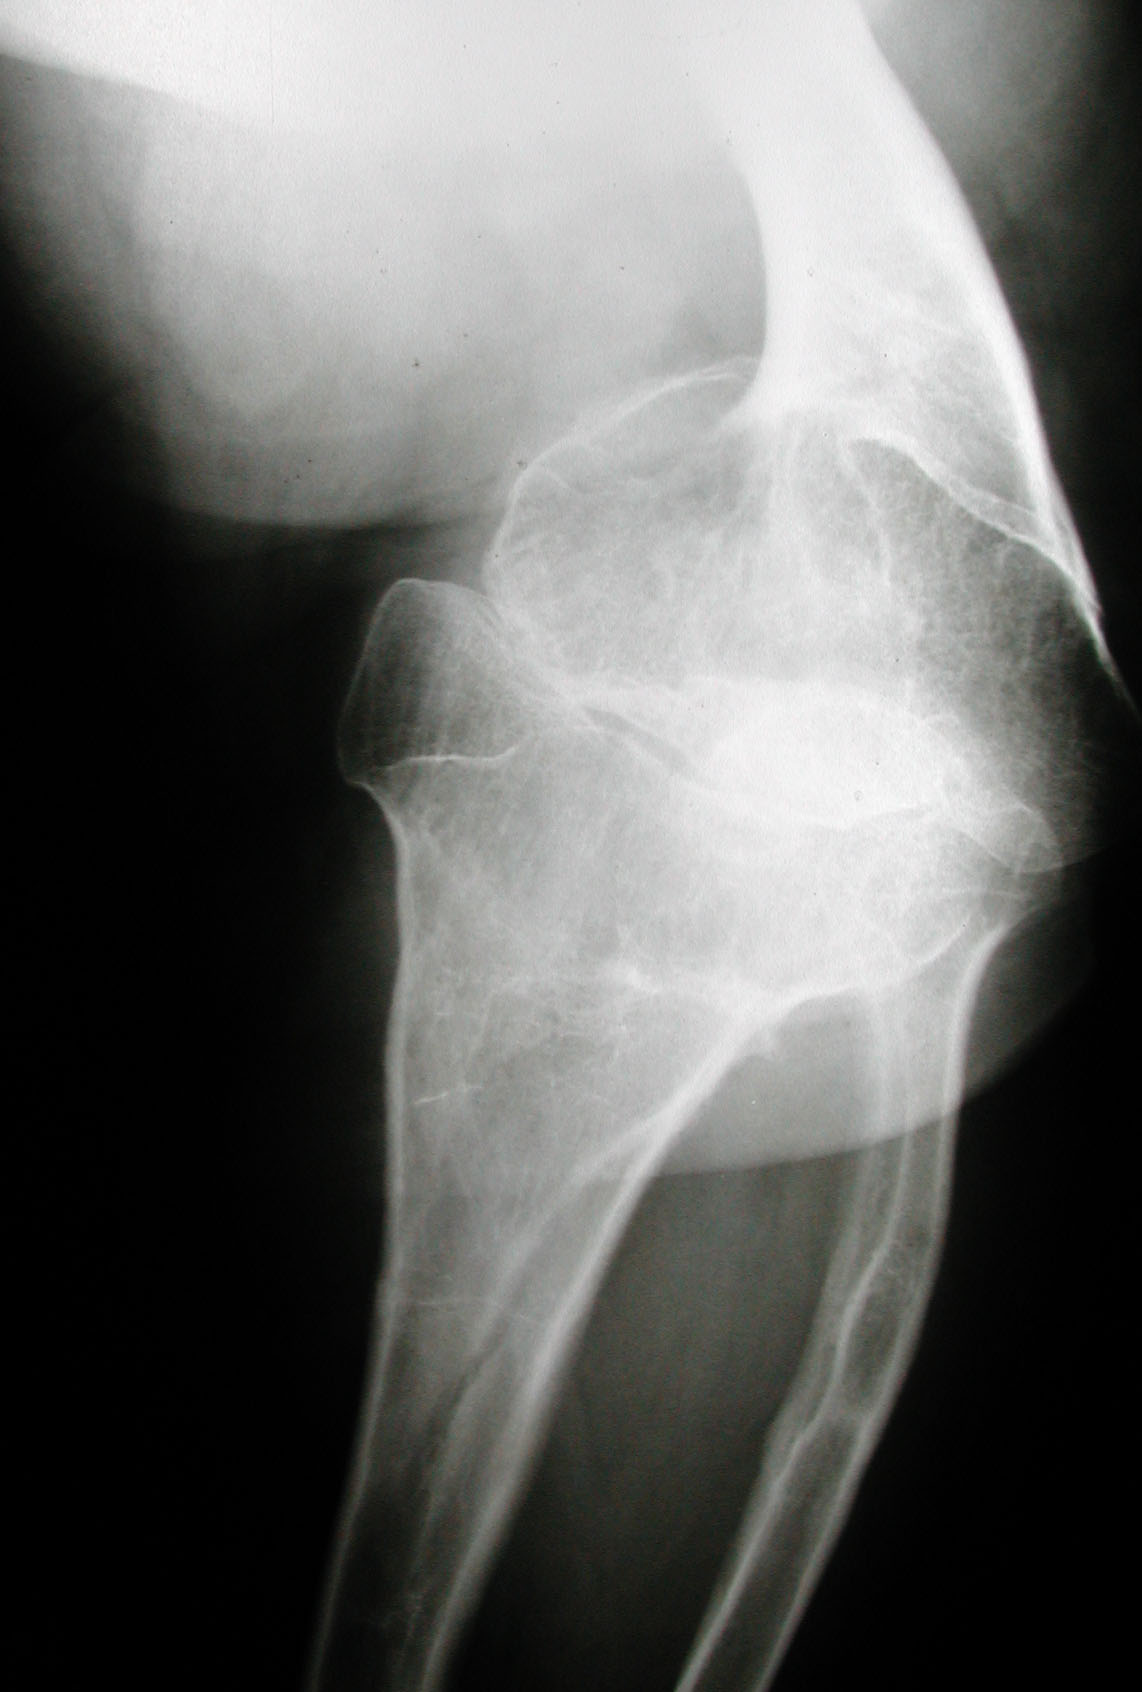

4. Crossan JF, Wynnes-Davies R, Fulfor GE. Bilateral failure of the capital femoral epiphysis: bilateral Perthes disease,

multiple epiphyseal dysplasia, pseudoachondroplasia, and spondyloepiphyseal dysplasia congenital and tarda. J Pediatric Orthop

1983;3(3):297-301.